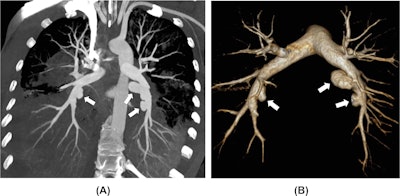

A 35-year-old woman with a history of multiple drug abuse presented with general discomfort, fever, chest pain, cough, and massive hemoptysis. Blood cultures were positive for Streptococcus anginosus, but no signs of endocarditis were found on echocardiography. (A) CT pulmonary angiogram maximum intensity projection (MIP) reformatting shows multiple pulmonary artery saccular outpouchings (white arrows) within the consolidated lower lobes. (B) 3D CT pulmonary angiogram reconstruction better depicts the saccular dilatations of the inferior lobar pulmonary arteries in keeping with infectious pseudoaneurysms (white arrows).